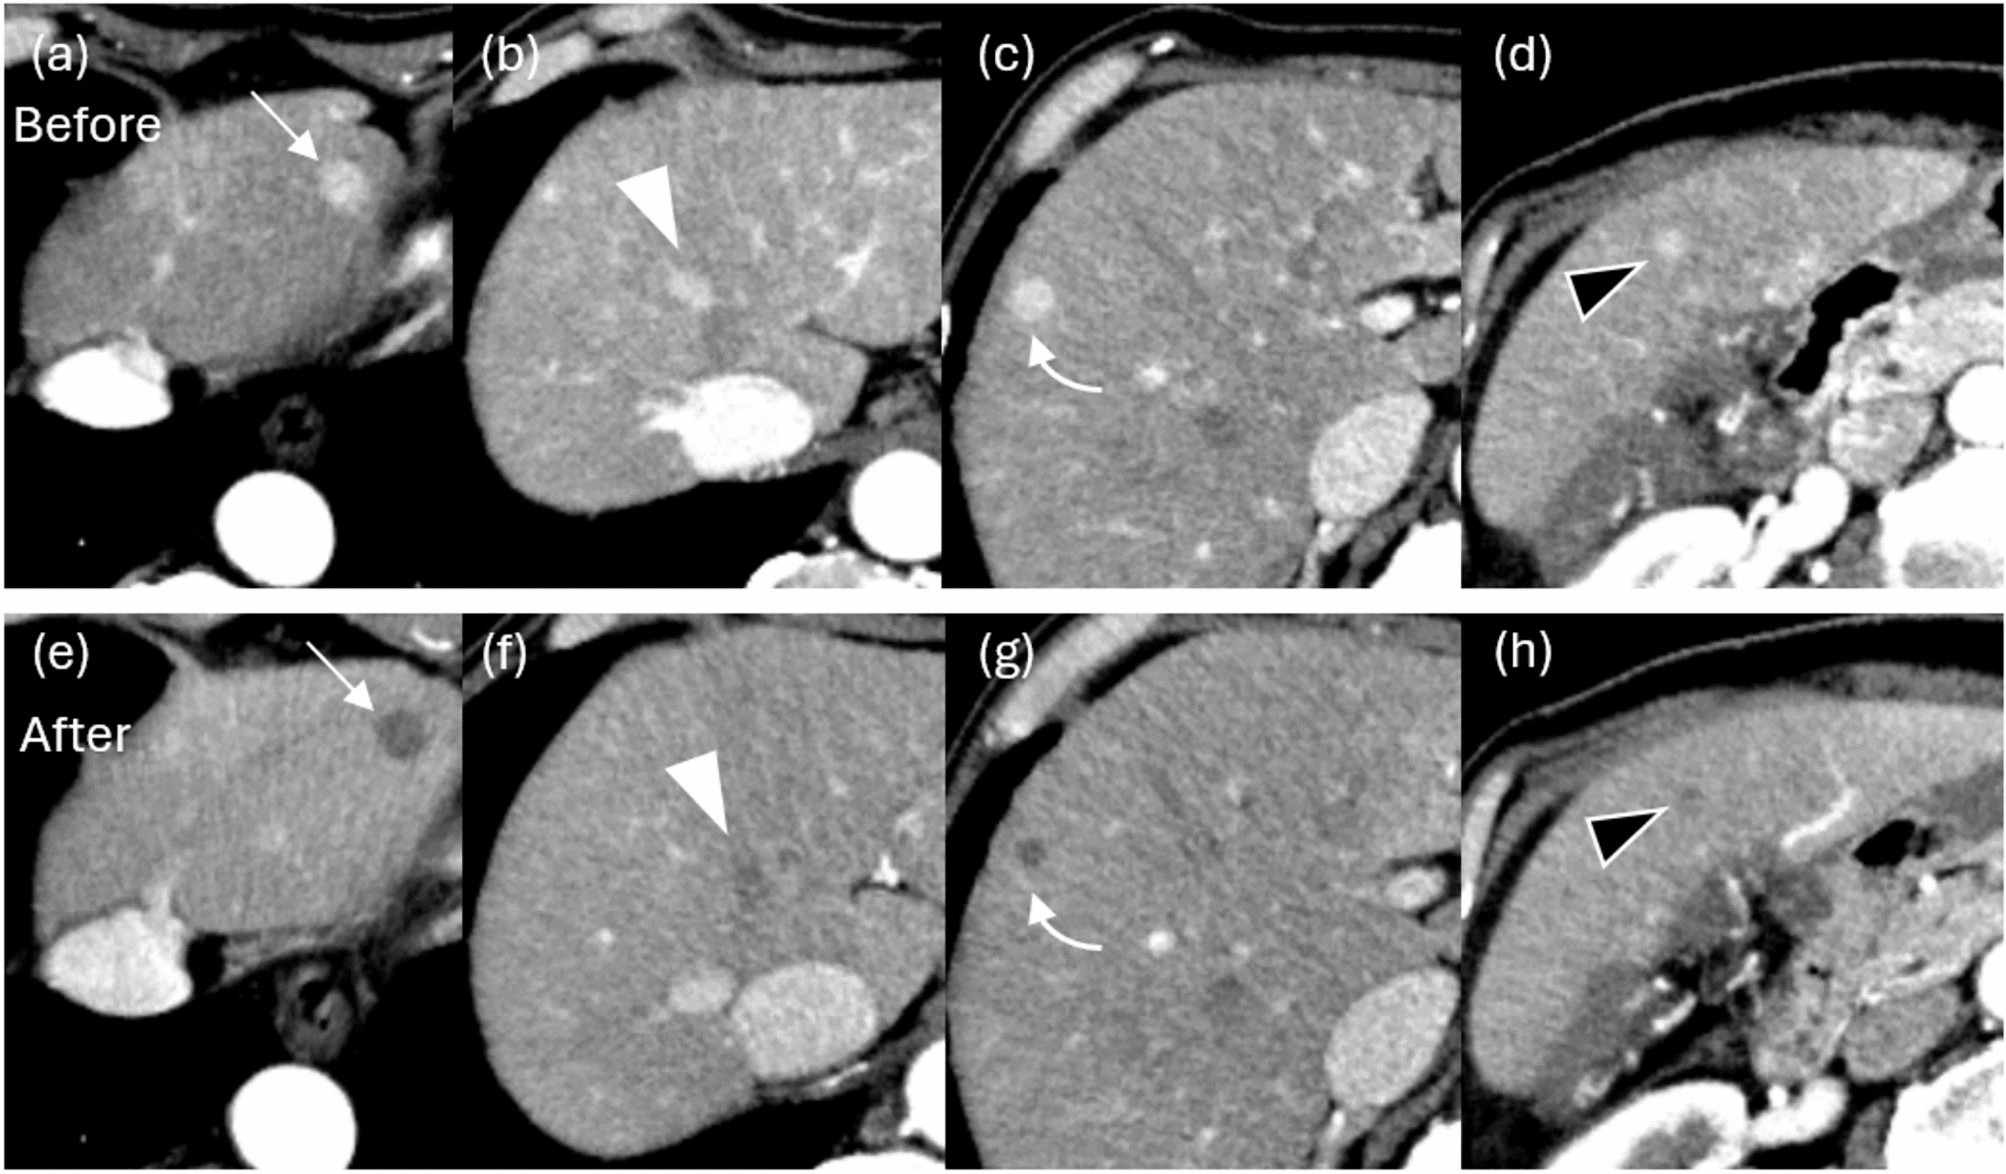

Fig. 5

Arterial phase of contrast-enhanced CT before (a, b, c, d) and after (e, f, g, h) BOAI-TACE in a 78-year-old man. Seven HCCs were found in the liver, including a 14 mm hepatocellular carcinoma (HCC) in S3 (arrow), a 13 mm HCC in S4/8 (white arrowhead), a 11 mm HCC in S8/5 (curved arrow), and a 6 mm HCC in S5 (black arrowhead). After treatment, the contrast effect of all lesions disappeared and complete response was obtained.